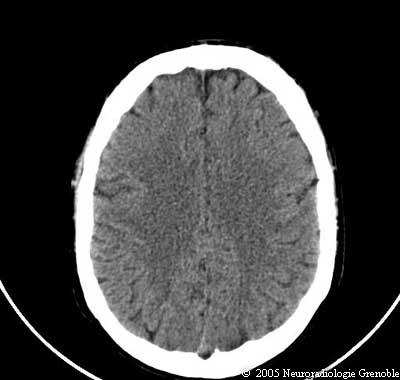

Radioanatomie TDM de l'encéphale

TDM cérébrale sans injection